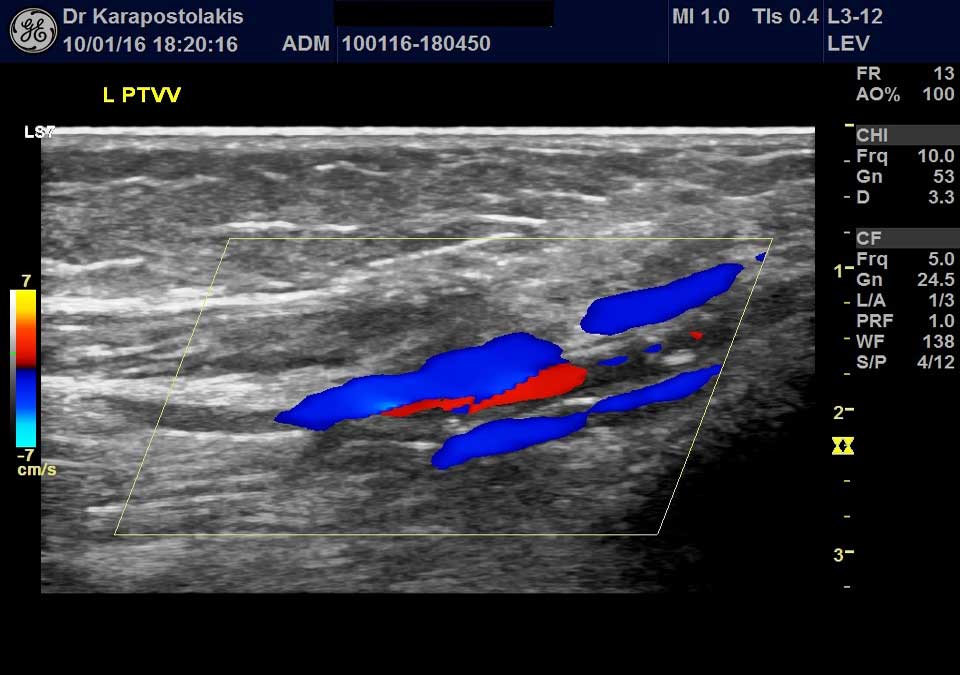

- Triplex καρωτίδων και σπονδυλικών αρτηριών, σφαγίτιδων

- Triplex κοιλιακής αορτής, λαγονίων αρτηριών, νεφρικών αρτηριών, σπληνοπυλαίου άξονα, σύνδρομο καρυοθραύστη

- Τriplex κοιλιακής αορτής, λαγονίων αρτηριών και φλεβών, νεφρικών αρτηριών, σπληνοπυλαίου άξονα